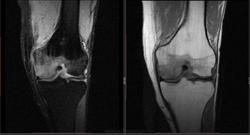

Мужчина 1963 г.р. Жалуется на боль в левом коленном суставе около 6 мес, в последний месяц стало совсем тяжко. Со слов заболел зимой, когда во время прогулки коленки сильно замерзли. Сам думаю на асептический некроз, но смущает множественность поражения.

Дмитрий, я в заболеваниях суставов не дока, но трабекулярный отек вкупе с выпотом может быть обусловлен воспалительными изменениями , но полностью начальные проявления аваскулярного некроза не могу отрицать.

я бы не поставил аваскулярный некроз. если исключена травма, дифференцировать с артритом.

Хрящ не поврежден, для артрита...